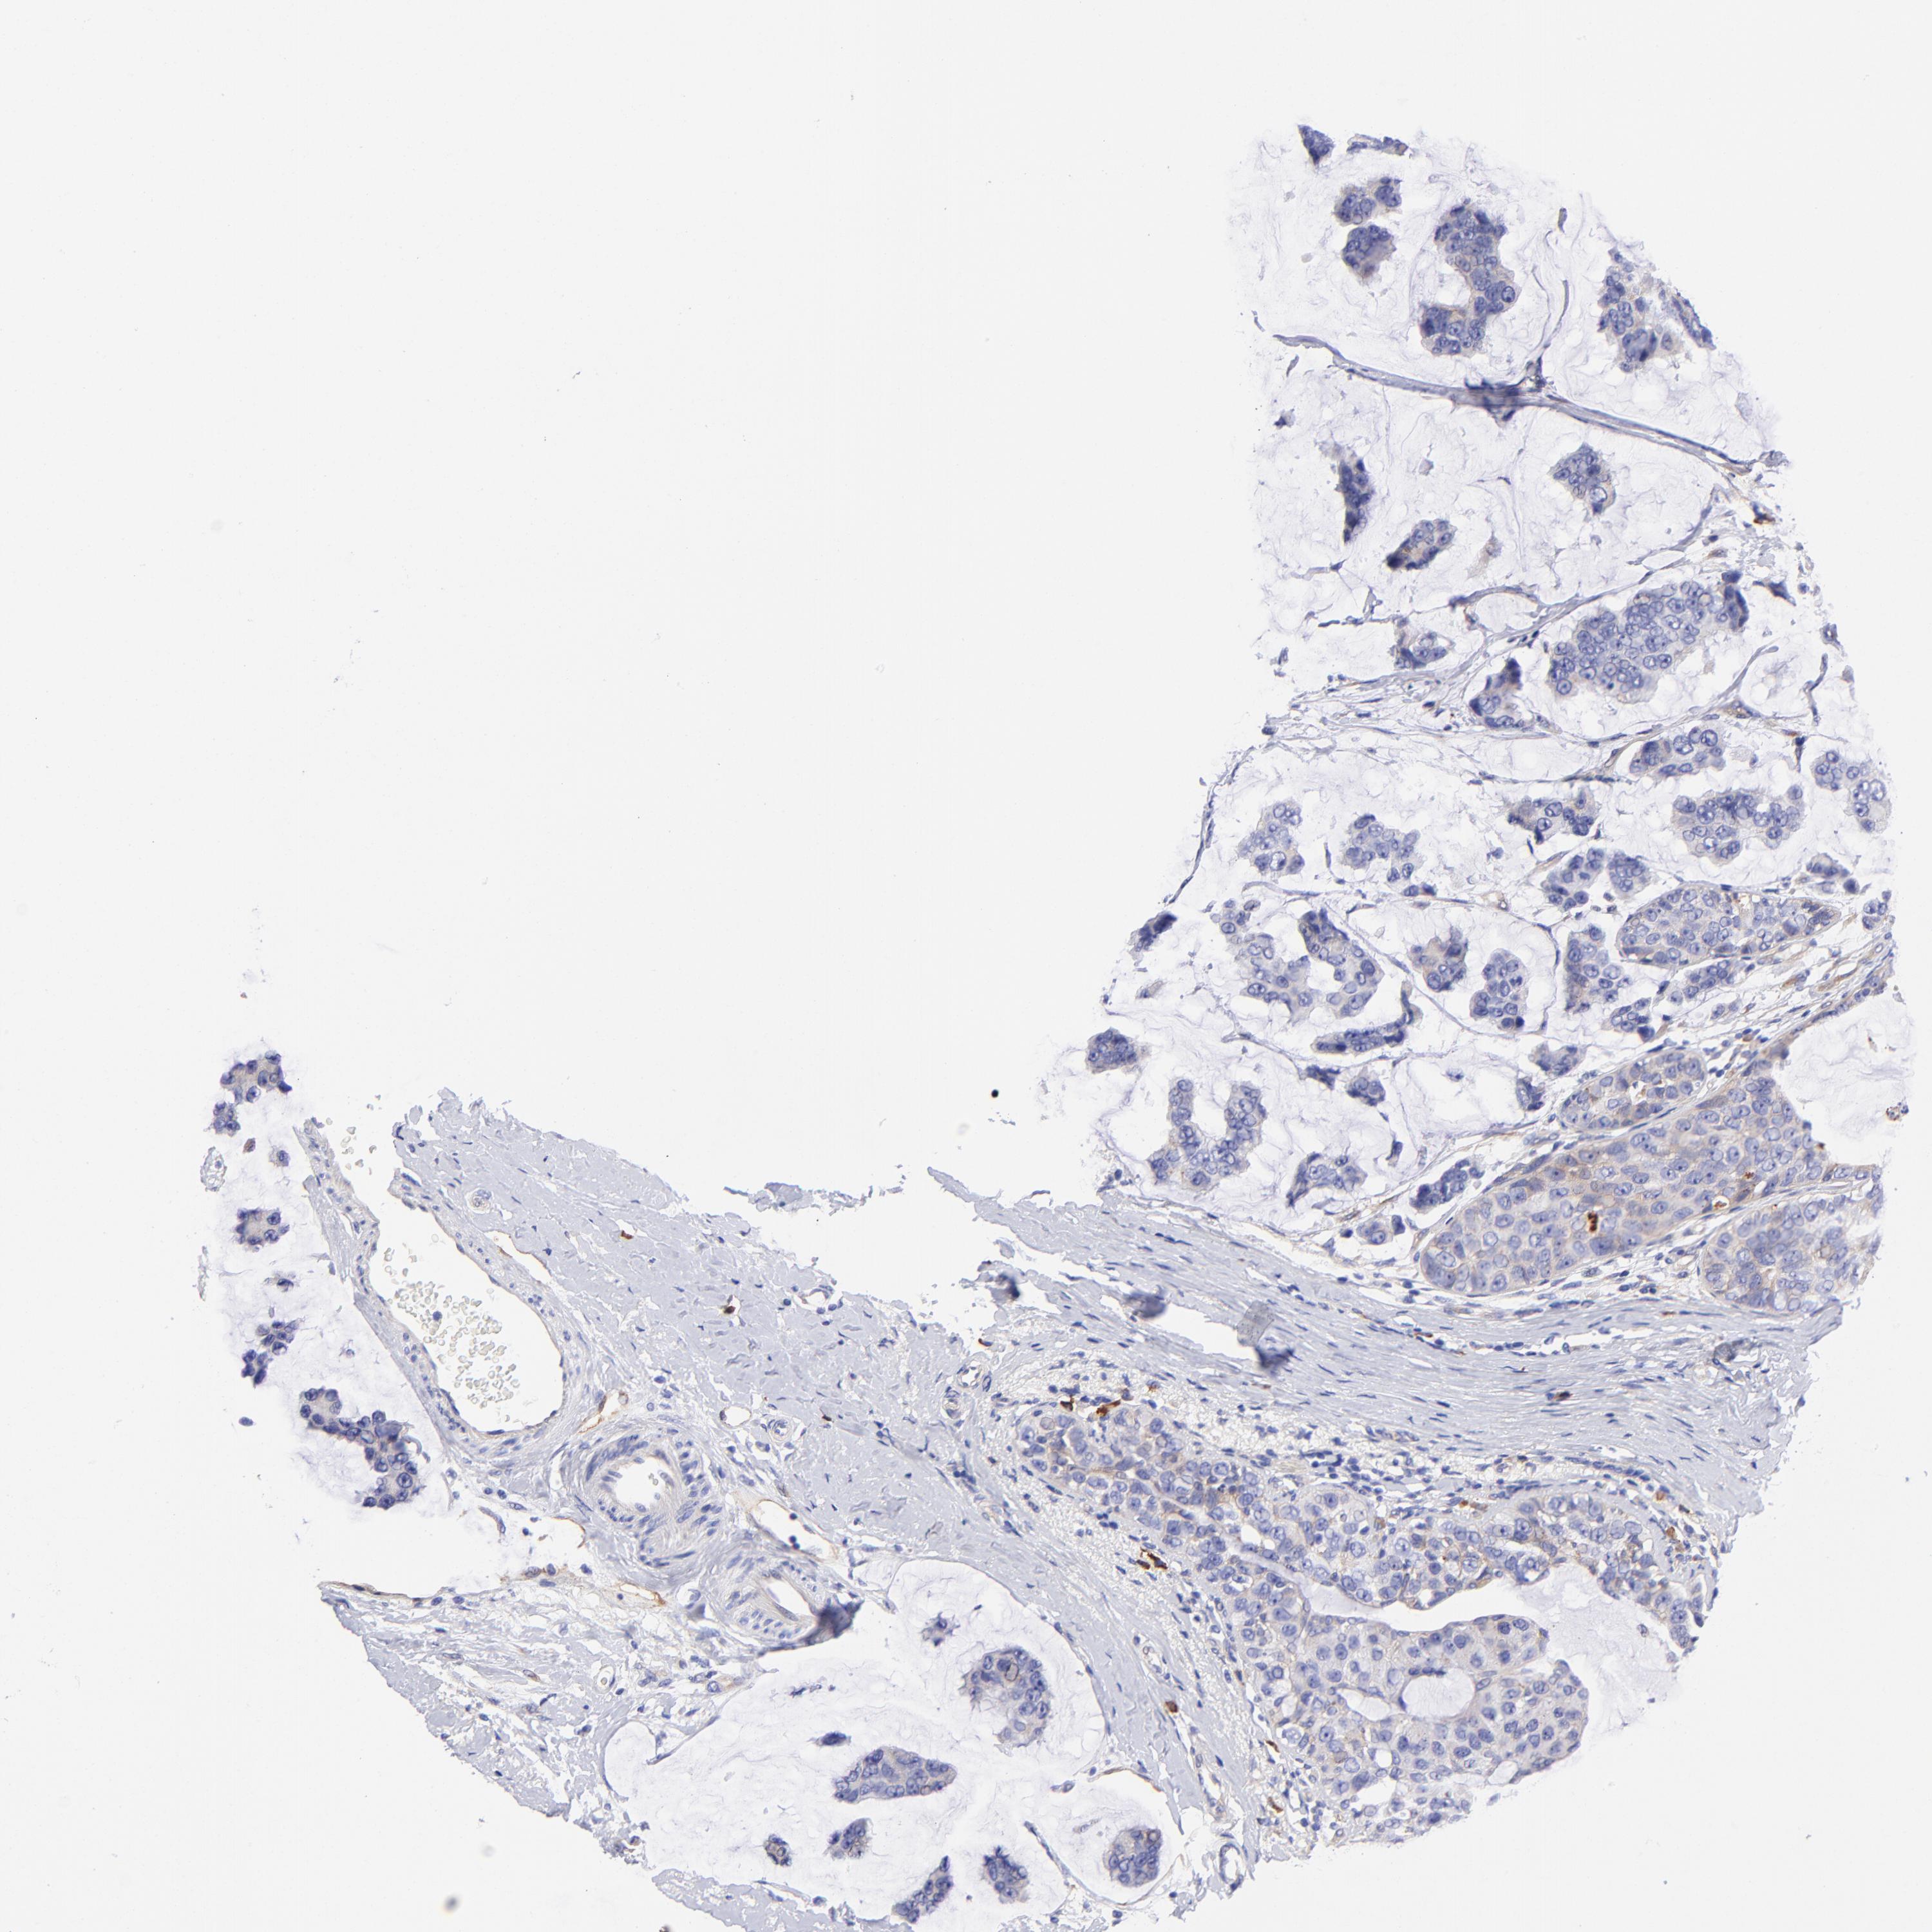

BRCA TCGA BRCA VALIDATION PROTEIN EXPRESSION